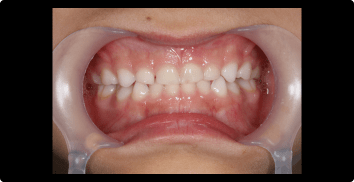

症例1:受け口の矯正治療

BEFORE

AFTER

症例概要

年代・性別

10歳代 女性

主訴

上下反対の噛み合わせが気になる

治療内容

ムーシールドを用いた矯正治療

治療期間

4ヶ月

治療のリスク

装置の装着時間を守らないと、治療結果が伴わない場合があります

治療費用

440,000円(税込)